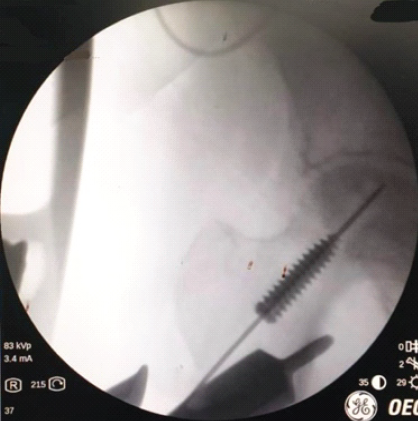

We present a case in which a metal interference screw became sunken within the femoral neck during bilateral hip core decompression and AALCO injection, as shown in Fig. 1.

Figure 1: Interference screw sunken in the femoral neck.